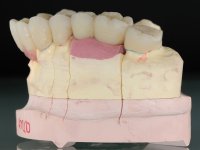

Alginate impressions were made at both arches arcades, accompanied by intermaxillary registration relations and collecting information with facial bow facial bow. In the laboratory, a provisional bridge with 13 elements in autopolymerizable acrylic was built, in which a metallic reinforcement was included. Teeth 1.7 / 1.4 / 1.3 / 2.2 / 2.3 / 2.4 and 2.6 were used as pillars. The metal-ceramic bridge was removed after performing longitudinal cuts with diamond burs. The dental abutments were reprepared and the temporary bridge was relined in the mouth with self-curing acrylic. After confection of the provisional bridge, a gingival epithesis was made using composite resin with gingival tonality in order to function as a mock-up, which allowed the patient to preview the possibility of using gingiva shade ceramics in the final work. This option was approved by the patient. Subsequently, the placement of two implants in the first quadrant was planned and executed. The provisional monoblock was removed for placement of the implants, and after surgery was again cemented provisionally. After the osseointegration period, the impressions were made to the maxilla. In the anterior zone, impregnated gingival retraction cords were used, and in the posterior areas, kaolin paste was used. Implant printing utilized the open tray technique. The printing material used was soft and regular putty addition silicone, both fast-setting. In the laboratory, the model of provisional restorations and the gingiva epithesis mock-up served as orientation for waxing the infrastructure. The plaster work model and the waxing of the infrastructure were placed in a laboratory scanner and yielded a digital work model, in which the scanning of the waxed infrastructure was superimposed. This overlay facilitated the CAD design of the Zr infrastructure. Subsequently, the CAD drawing for a CAM milling process provided the Zr pieces. The infrastructure was pigmented with a pinkish coloration, which favors the subsequent placement of gum shade ceramic. During the modeling of the infrastructure, the need to increase the occlusal wear on tooth 1.4 was detected. This was done in the real working model cast and an acrylic wear control guide was created, which accompanied the proof of the infrastructures. Corrective wear and Zr parts test were performed in mouth. During the test, the color choice of the gum shade ceramic was reassessed. The treatment was finished in the laboratory, and after approval by the patient, was definitively placed in the mouth.